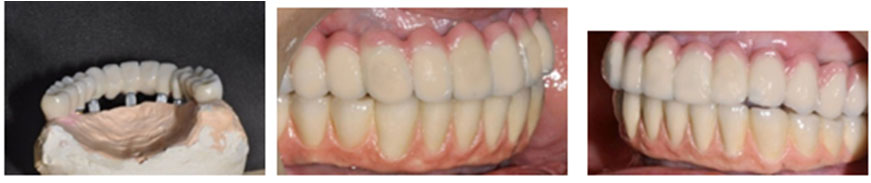

After 5 months, all the implants were uncovered. They were evaluated for mobility, bone loss or any infection. Impression transfers were attached to all the implants and open tray impression was taken with addition silicone material (Dentsply). Each implant connection was verified with x-ray and evaluated before making the impression. All the impression transfer posts were splinted together with resin (Pattern Resin) and cut initially and then again joined to counter the expansion of the material. Definitive cast was poured in type IV stone. Diagnostic casts were prepared for both the maxilla and mandible. Standard prosthodontic principles were followed, which included maxilla-mandibular relations. As all the implants were relatively parallel, multiunit abutments were used for optimal positioning for screw access channels in the final prosthesis. A cast metal framework was fabricated over the abutments from silver palladium alloy (Figure 3, a and b). The passivity and fit of the framework was tried in the patient mouth in both arches. Sheffield screw testing was carried out for the framework check in the mandible. Bite registration was taken and recorded (O-bite). A final prosthesis try-in was performed to confirm accurate transfer of teeth, phonetics and mutually protected occlusion. The final prosthesis was fabricated in the porcelain fused-to-metal for both arches. The occlusal screws of maxillary and mandibular prosthesis were tightened to 15 Ncm. The screw channels were filled with warm gutta-percha resin and sealed with composite resin (Figure 4, a, b and c). The patient was given postoperative cleaning instructions using Proxa brushes and powered water irrigation system. The patient was kept on 3-month follow-up recalls for periodontal maintenance for 5 years. During these visits periodontal assessment was carried out with routine supragingival and subgingival debridement. Oral hygiene was further reinforced if needed. Prosthetic complications were assessed, too. The patient was quite satisfied with the prostheses of both arches. At 5-year recall, all the implants were stable and the prostheses were devoid of any complications. The periodontal condition of the remaining natural teeth was quite stable. The radiographs taken around implants revealed bone levels within normal limits. After 5 years, 6-month recall visits were scheduled for the next five years.

japid-11-39-g003

Figure 3. (a) Complete healing after osteotomy of six implants; (b) Framework for the prosthesis.

japid-11-39-g004

Figure 4. (a) Porcelain screw-retained prosthesis; frontal view; (b) Lateral view; (c) Orthopantomogram of the prosthesis.